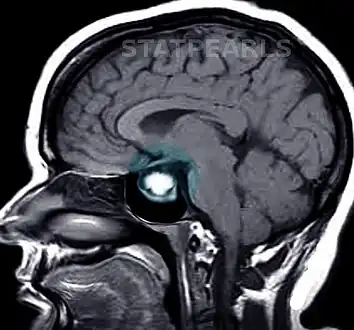

A doctor will test for prolactin blood levels in women with unexplained milk secretion (galactorrhea) or irregular menses or infertility, and in men with impaired sexual function and, in rare cases, milk secretion. If prolactin is high, a doctor will test thyroid function and ask first about other conditions and medications known to raise prolactin secretion. The doctor will also request a magnetic resonance imaging (MRI), which is the most sensitive test for detecting pituitary tumors and determining their size. MRI scans may be repeated periodically to assess tumor progression and the effects of therapy. CT scan also gives an image of the pituitary, but it is less sensitive than the MRI.

In addition to assessing the size of the pituitary tumor, doctors also look for damage to surrounding tissues, and perform tests to assess whether production of other pituitary hormones is normal. Depending on the size of the tumor, the doctor may request an eye exam with measurement of visual fields.

Prolactinoma on MRI